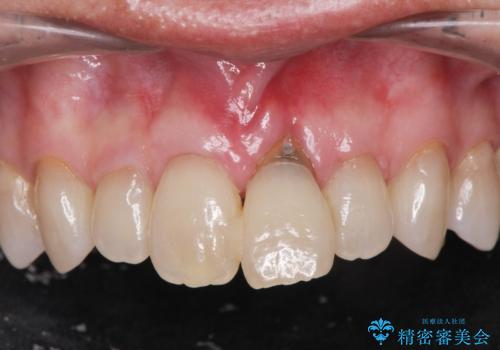

前歯の隙間とへこみが舌で触ると気になる|矯正治療は絶対にしたくない|抜歯即時インプラント+オールセラミッククラウンで審美修復

外科処置は一度だけ|抜歯即時インプラントで短期間で自然な見た目へ

前歯の変色が気になる〈セラミッククラウン〉